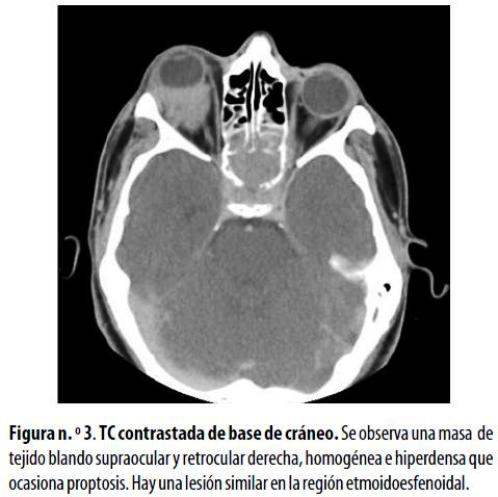

Hombre de 18 años en recaída de LMA, quien consultó por dolor orbitario y proptosis derecha. La TC mostró una masa homogénea de tejido blando supraocular y retrocular en la órbita derecha, que ocasionaba la proptosis, y lesión erosiva en la región esfenoetmoidal (figura n.º 3) . En vista de la progresión de sus síntomas visuales fue sometido a radioterapia con buena tolerancia; sin embargo, no se describieron los controles clínicos adicionales después de la terapia.